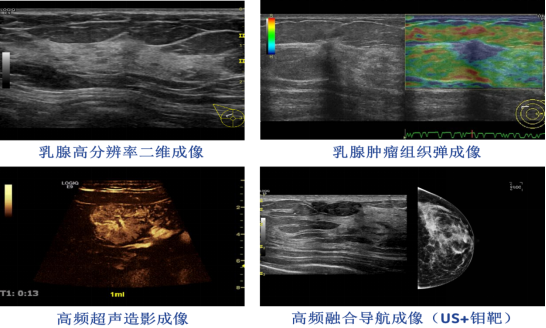

對(duì)乳腺結構顯示非常清晰,結合高(gāo)敏感性的(de)彩色多(duō)普勒顯示♥Ωε及頻(pín)譜多(duō)普勒可(kě)γ☆分(fēn)析病竈內(nèi)的(de)血流參數(shù),在無<≈βλ創的(de)情況下(xià)做(zuò)出β&β準确診斷;同時(shí)能(néng)對(du♥"ì)病竈內(nèi)微(wēi)循環灌注情←γ↑況給予各種定量分(fēn)析;組織彈性成像可(kě)對(duì)乳腺病竈的(de)組織質地(dì×)得(de)出判斷和(hé)分(fēn)析。對(duì)肌肉骨骼等一(yī)些(xiē)淺表組織具有(y≈<₹•ǒu)極佳的(de)成像效果,對(duì)細小(x∞λ≠iǎo)血供進行(xíng)觀察;彈性成像技(jì)術(shù)又(yòu)¥↔能(néng)對(duì)組織的(de)組織質地(dì)進行(xíng)觀察,φφ≥得(de)到(dào)組織變形的(de)佐證。